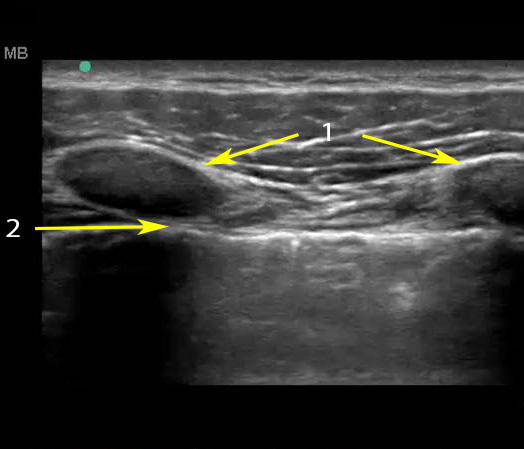

肺滑行 HFL 图像

肋骨

胸腔线